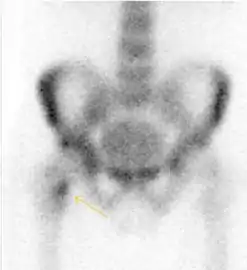

Nuclear Medicine

Bone scanning in people with hip pain can be complementary to other imaging studies, mainly in indeterminate bone lesions to clarify whether it is an active lesion with abnormal radiotracer accumulation. Nevertheless, MRI has replaced scintigraphy in the diagnosis of most of these conditions. An example is stress or insufficiency fractures: increased uptake is usually present in around 80% of fractures within 24 h, and 95% of fractures reveal activity by 72 h following trauma, showing an overall sensitivity of 93% and specificity of 95%. MRI is superior to bone scans in terms of sensitivity (99%-100%) and specificity (100%). Moreover, a bone scan does not provide detailed anatomical location of the fracture, and further imaging is usually required.[1]

Figure 10:

- Stress femoral neck fracture in a young athlete barely visible in X-ray film as a sclerotic line (arrow)[1]

- In this case, Tc 99 scintigraphy shows a band of uptake[1]

- Furthermore, T1 (left) and DP fat saturated (right) weighted MR images showed the fracture line and a pattern of edema.[1]